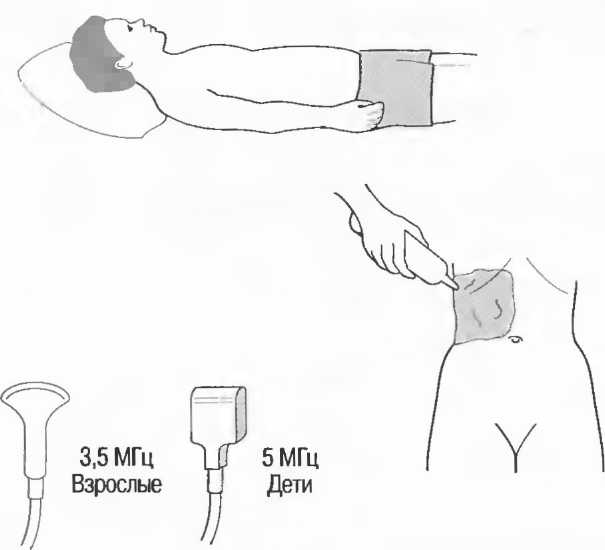

1. Подготовка

Пациент не должен пить и есть в течение 8 ч перед исследованием. Если жидкость необходима для предотвращения дегидратации, можно давать пациенту только воду. При острой симптоматике исследование можно проводить без подготовки. Детям, если позволяют клинические условия, пища и вода не даются в течение 3 ч до исследования.

При более углубленном исследовании, если нет клинических противопоказаний, может быть полезным дополнительный прием воды, особенно при исследовании поджелудочной железы, нижних отделов живота и таза.

2. Положение пациента. Пациент может лежать в удобной позе на спине. Под голову можно положить маленькую подушку, в случае выраженного напряжения передней брюшной стенки подушечку можно поместить также под колени пациента.

Намажьте живот гелем.

Пациенту разрешается дышать спокойно, однако при исследовании отдельных органов требуется задержка дыхания на вдохе.

3. Выбор датчика. Используйте датчик 3,5 МГц для взрослых и датчик 5 МГц для детей и худых взрослых. Предпочтительны конвексные или секторные датчики.